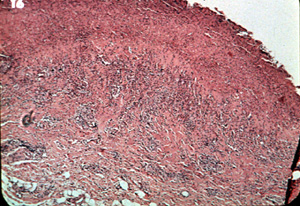

Inflamación

La intensa inflamación crónica en el tejido conjuntivo también tiene una tendencia a bloquear la reflexión de la luz  roja. Esta micrfotografía ilustra como la inflamación crónica puede evitar también la reflexión de la luz. Tiene el efecto de espesar el área entre la superficie y los vasos sanguíneos subyacentes.